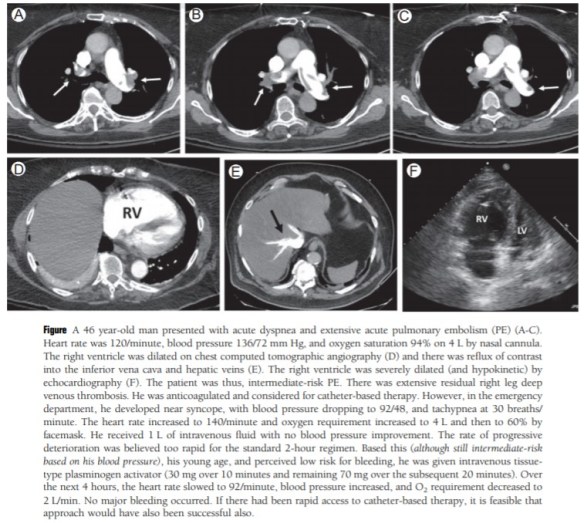

“For several decades, clinicians and clinical trialists have worked toward a more aggressive, yet safe solution for patients with intermediate-risk PE. Standard-dose thrombolysis, low-dose systemic thrombolysis, and catheter-based therapy which includes a number of devices and techniques, with or without low-dose thrombolytic therapy, have offered potential solutions and this area has continued to evolve. On the basis of heterogeneity within the category of intermediate-risk as well as within the high-risk group of patients, we will focus on the use of systemic thrombolysis in carefully selected high- and intermediate-risk patients. In certain circumstances when the need for aggressive therapy is urgent and the bleeding risk is acceptable, this is an appropriate approach, and often the best one.”